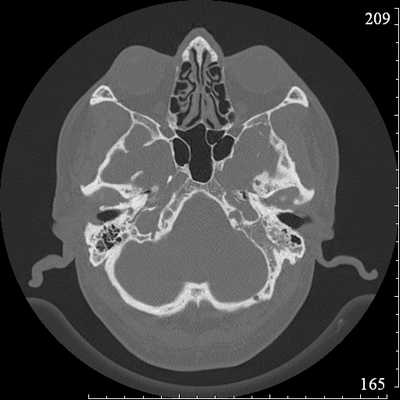

Во время КТ получают послойные снимки височной кости и окружающих тканей в трех плоскостях. Толщина среза составляет всего несколько миллиметров, что позволяет врачу-рентгенологу рассмотреть не только все анатомические образования, но и минимальные патологические изменения.

Снимок (томограмма) височных костей в осевой проекции

— На КТ-снимке мы наблюдаем структуры наружного, среднего и внутреннего уха (слуховые косточки, конфигурацию слухового прохода). Кроме того, можно оценить костные элементы, а также воздушные полости височной кости на предмет нарушения их пневматизации (заполнения воздухом). На основании этих данных мы делаем вывод, являются ли выявленные изменения причиной недуга, который беспокоит пациента.